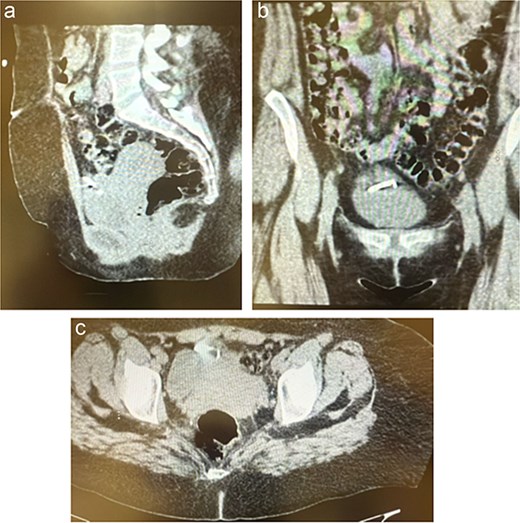

Initial laboratory work-up revealed a normal white blood cell count. Urinalysis was positive for leukocytes and nitrites, indicating a urinary tract infection. A plain abdominal X-ray did not clearly visualize the IUD but raised suspicion for its extrauterine location (Fig. 1).

A plain abdominal X-ray was performed, which visualize the IUD with suspicion for its extrauterine location.